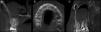

Caso clínicoVarón de 28 años, diagnosticado con acalasia y sometido a cirugía laparoscópica esofágica con intubación oro-traqueal hace 10 días. A los 5 días postoperatorios, presentó dolor agudo y sensación de disestesia en el paladar duro. Clínicamente se aprecia una lesión eritematosa que evoluciona con aumento de volumen, de 1,5×1,0cm en hemipaladar izquierdo (fig. 1), de consistencia fluctuante. El segundo molar superior izquierdo con restauración ocluso-distal de resina compuesta cercana a cámara pulpar y dolor agudo irradiado en hemimaxilar izquierdo, a la masticación y percusión. Como tratamiento inicial, se indica trepanación de la pieza dentaria (inicio tratamiento endodóntico). Ante el curso, sin modificaciones de la sintomatología ni evidencia de drenaje, se solicita una tomografía computarizada cone-beam (CBCT) y biopsia incisional de la lesión. La imagenología no evidenciaba compromiso óseo (fig. 2). El informe histopatológico describe mucosa palatina en parte recubierta por epitelio plano pluriestratificado, con islotes de epitelio escamoso, y algunos ductos glandulares, asociado a tejido glandular con signos de necrosis, persistiendo solamente la pared de las células acinares, con un infiltrado mononuclear y algunos neutrófilos (fig. 3), lo cual indicaba una lesión de origen posiblemente traumático. El diagnóstico fue la SN, la lesión remitió espontáneamente un mes posterior a la biopsia (fig. 4).

A) Microfotografía de corte histológico tinción hematoxilina-eosina ×100. Se observan islotes epiteliales escamosos adyacentes a ductos glandulares muy dilatados con infiltrado mononuclear entre ellos. B) Se observa islotes epiteliales escamosos y también ductos y acinos, estos últimos con pérdida de sus núcleos y citoplasmas disgregados, con infiltrado linfocitario entre ellos. Tinción hematoxilina-eosina ×400.